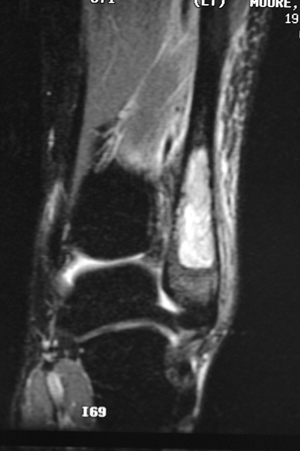

Figure 6.2-8 Magnetic resonance imaging shows marrow replacement with tumor. This was diagnosed as a Ewing sarcoma.

Figure 6.2-9

The patient was treated with wide resection and chemotherapy. No

reconstruction was performed, and no instability of the ankle was noted

on follow-up examinations. -